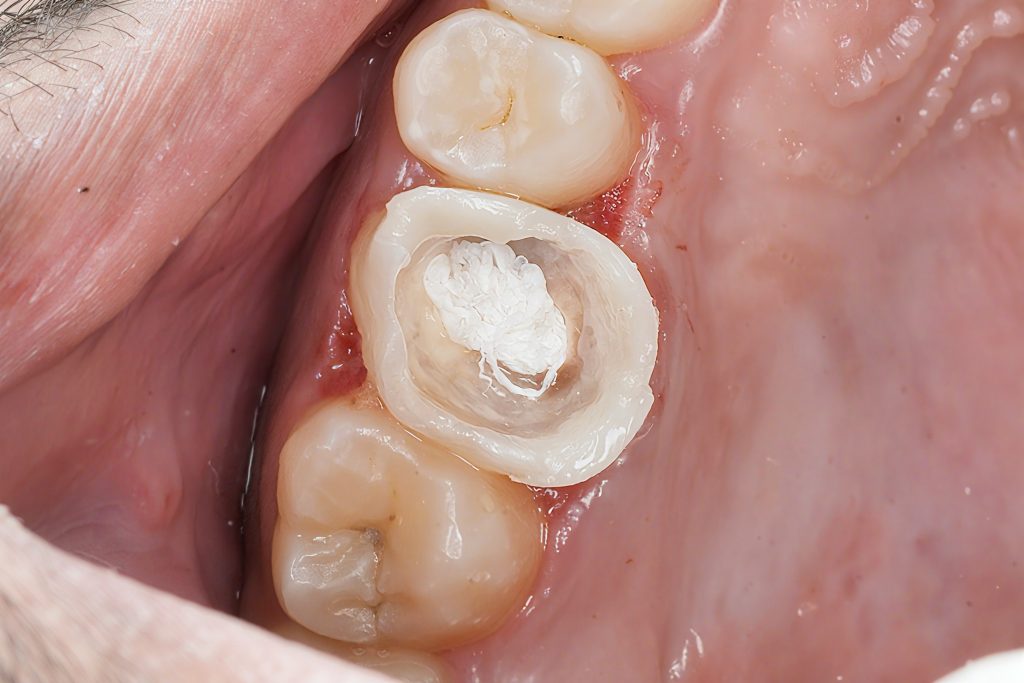

4. CORE BUILDUP & INTERNAL REINFORCEMENT

Composite Build-Up

A controlled build-up was done using:

- 3M Easy Match Shades for dentin & enamel

- Natural saturation using Tokuyama Estelite Ocher Stain for warmth

Fiber Reinforcement (If required)

EverX Posterior or Ribbond may be used in cases with thin cusps for internal support.

5. PREPARATION FOR COMPOSITE ONLAY

Minimal preparation was done:

- 1.5–2 mm reduction of functional cusps

- Smooth, rounded internal angles

- Supragingival margins after DME

- No unnecessary removal of sound enamel

Onlay preparations are ideal because they preserve enamel, improving bond strength and tooth longevity.